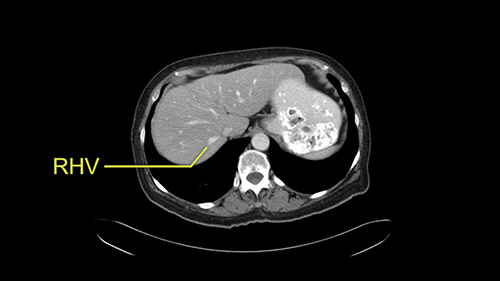

So I would then focus on the hepatic outflow because that’s the way we do the operation is by mobilizing the liver. So the vena cava looks quite normal. The right hepatic vein looks quite normal. There are no large additional outflow veins from the right lobe which would generate slowing down moments. The hepatic artery is unremarkable and is not usually an issue we can define the anatomy quite clearly at surgery.

Coming up a little bit higher. There’s a little bit of biliary dilatation as well. On the right side of the liver. Which may be nothing but it may be an indicator or harbinger of nodal disease in the hepatoduodenal ligament so something to be aware of. If the enzymatic liver function tests are normal and there’s no evidence of a stone in the common bile duct on cross sectional imaging you wouldn’t need to do anything about it but just to be aware of that.![[RHV]](jpg/preop_as_p4.jpg)

So we’re going through the liver segments now. Here we’ve got the inflow; here’s the main portal vein, right anterior sectoral portal vein, right posterior sectoral portal vein there. Here’s the main here going to the left lobe first of all. So that’s 3 and 2 there, they look clear, and there’s a good size of the left lobe with a good girth. So 3 and 2 look clear. There are usually more feedback branches from the left portal vein to segment 4b but that also looks relatively clear. There’s a little more disease over on the right side there. So that would be...right hepatic vein here...that’s Segment 7. So we’ve got disease in 7, 5, probably in 6 on the right side; at least 3 lesions. That’s the distribution of the lesions.![[Ant. RPV] [Main PV] [Post. RPV]](jpg/preop_as_p5.jpg)